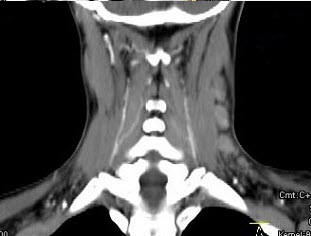

女,19岁,发现左颈部无痛性肿块2年余,可活动,CT如图所示,最可能诊断为()。

A、淋巴结炎

B、淋巴瘤

C、转移癌

D、淋巴结结核

E、巨淋巴结增生症

E